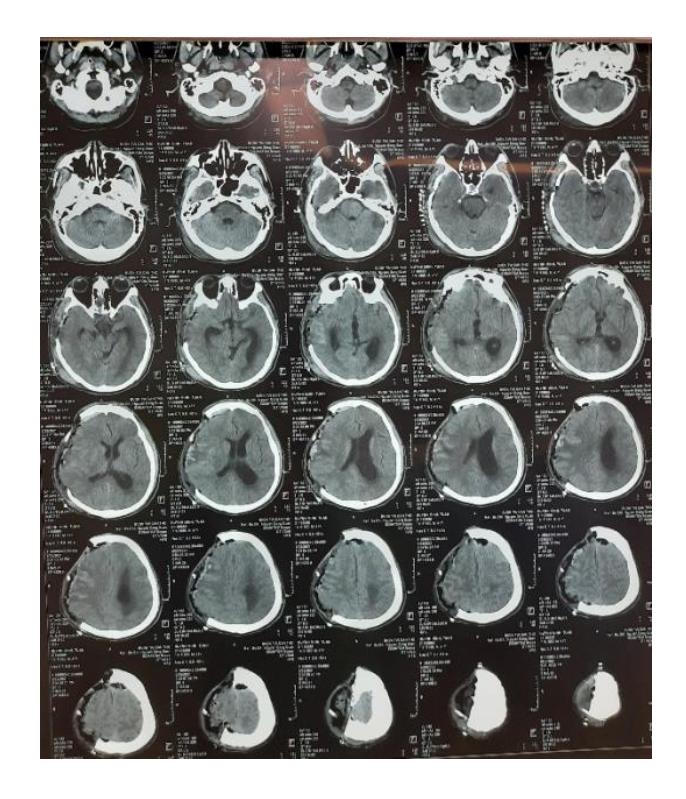

Bệnh nhân tỉnh, tiếp xúc tốt |

Đối với bệnh nhân này, bệnh xác định cần mổ cấp cứu, không thể chậm trễ. Ê kíp phẫu thuật với sự hỗ trợ của kính vi phẫu đã lấy trọn toàn bộ khối u đồng thời bảo tồn các mạch máu não. Hiện, bệnh nhân đã tỉnh, tiếp xúc tốt. Sự hồi phục kỳ diệu của bệnh nhân mang lại niềm vui không thể diển tả của tập thể thấy thuốc bệnh viện và người nhà bệnh nhân.